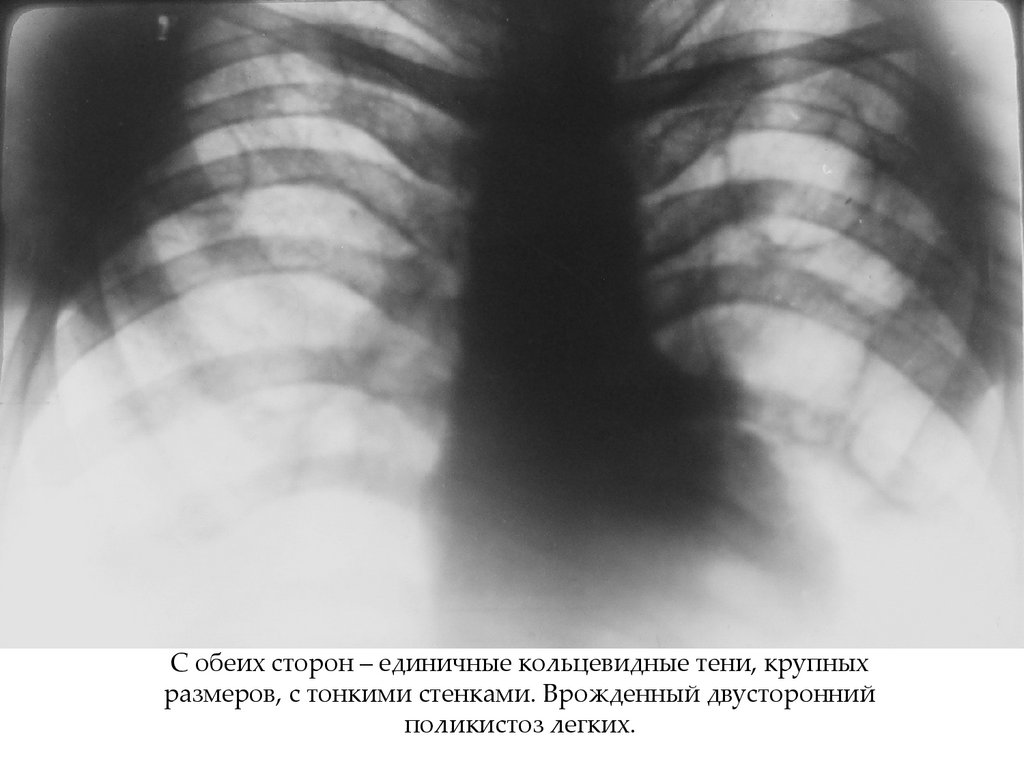

20. Кольцевидная тень – изображения кольца в ортогональной проекции.

Характеристики:

•Наружный диаметр;

Разница между ними

равна толщине стенки

•Внутренний диаметр;

•Количество: одиночная/единичные/многочисленные;

•Внутренний контур: четкий, ровный/неровный,

бугристый, бухтообразный, секвестроподобный.

•Плотность стенки: выраженная/умеренная

С обеих сторон – единичные кольцевидные тени, крупных

размеров, с тонкими стенками. Врожденный двусторонний

поликистоз легких.